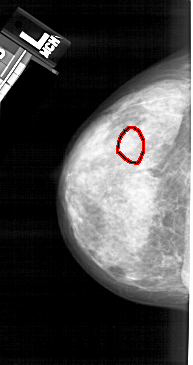

A_1338_1.LEFT_CC

FILE: A_1338_1.LEFT_CC.OVERLAY

TOTAL_ABNORMALITIES 1

ABNORMALITY 1

LESION_TYPE CALCIFICATION TYPE AMORPHOUS DISTRIBUTION CLUSTERED

ASSESSMENT 4

SUBTLETY 4

PATHOLOGY BENIGN

TOTAL_OUTLINES 1

BOUNDARY